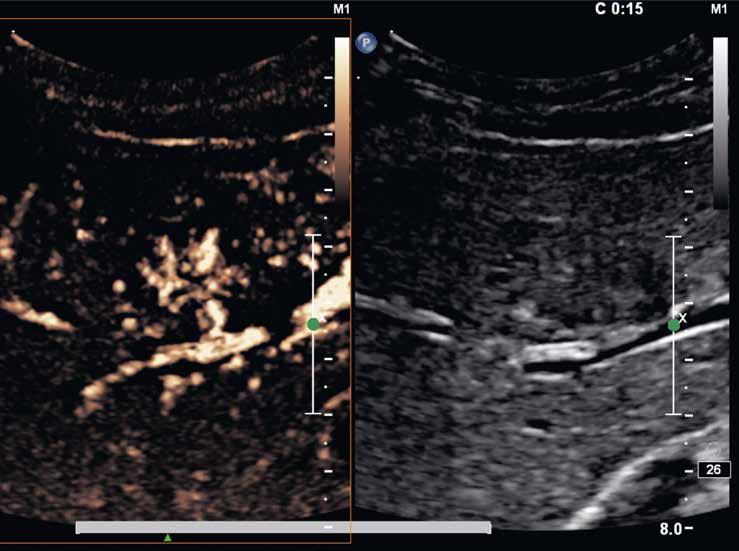

Na CEUS je v arteriální fázi patrný v levé polovině obrázku typický centrifugální charakter sycení ložiska, které je vidět v pravé polovině obrázku v B -módu (jako hypoechogenní) (6–8). Na CT (9) i MR (10) se ložisko (z obr. 4, 5) sytí homogenně, vyjma centrální vazivové jizvy, která zůstává hypodenzní.

Po aplikaci kontrastní látky se ložisko v arteriální fázi homogenně sytí (96–100 %) (obr. 6–10). Sycení je typicky intenzivní, ale na krátkou dobu, a ve 40 % případů –i když v některých publikacích se popisuje až u 90 % případů – může být patrný jeho loukoťovitý charakter („spoke-wheel pattern“) (obr. 6–8). Ten je zřejmý u větších

Pro FNH je typická centrální jizva, která se v arteriální fázi většinou nesytí; sytí se v portální a pozdní fázi (obr. 9, 13). Zobrazíme ji v 60–84 % případů. Od jizvy mohou vybíhat do periferie tenká septa. Jizva může být velmi malá, až nedetekovatelná.